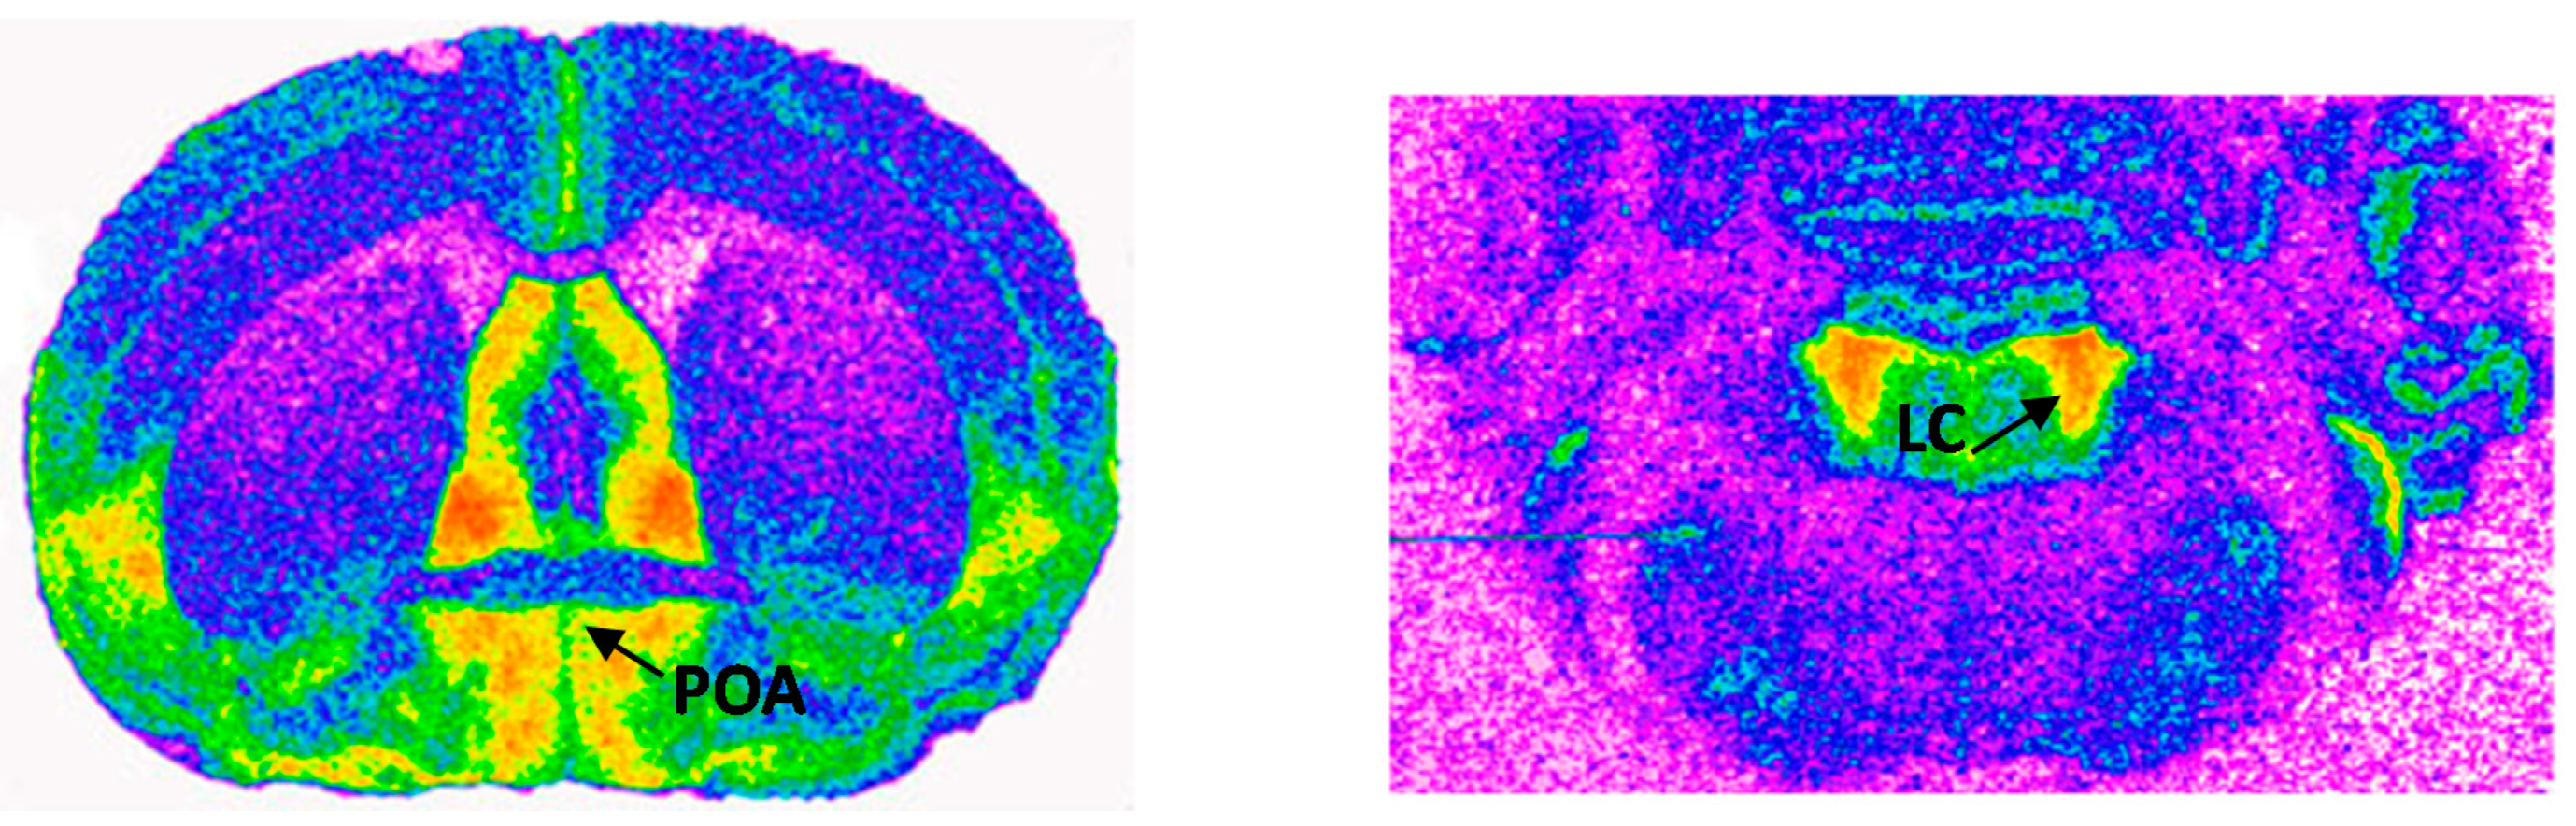

2.5. Effects of Prenatal Exposure to BPA on Receptor Density and Affinity in the Locus Coeruleus

2.6. Effects of Prenatal Exposure to BPA on Receptor Density and Affinity in the Medial Preoptic Area

4.6. Receptor Autoradiography and Quantification